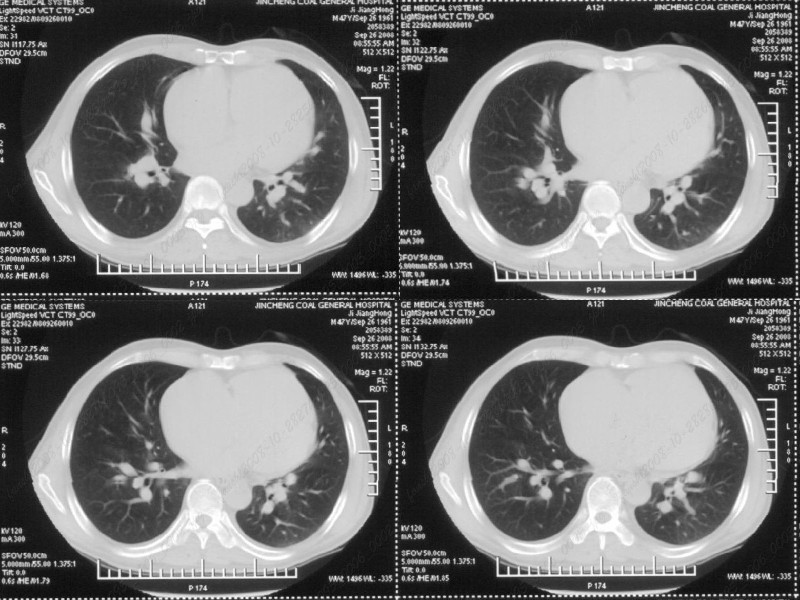

男性,47岁。胸部不适一年,ct检查发现右胸膜下结节。http://www.radida.com/bbs/forum.php?mod=viewthread&tid=46094

考虑右下胸膜的炎性结节,

右前胸膜下小结节,边缘有小纤维条索影与胸膜粘连,考虑如炎性假瘤之类慢性病变可能。期待二周后的结果。

右下肺胸膜下小结节,强化不明显。建议定期观察!

考虑心脏疾患引起的右侧斜裂增厚。

右肺静脉充盈缺损,左心房体积小,右肺动脉远端动脉充盈缺损,右肺血管影细小,考虑;右肺动脉远端栓塞.

右肺中叶外侧段占位,考虑周围型肺癌伴局限性肺气肿,不除外炎性假瘤